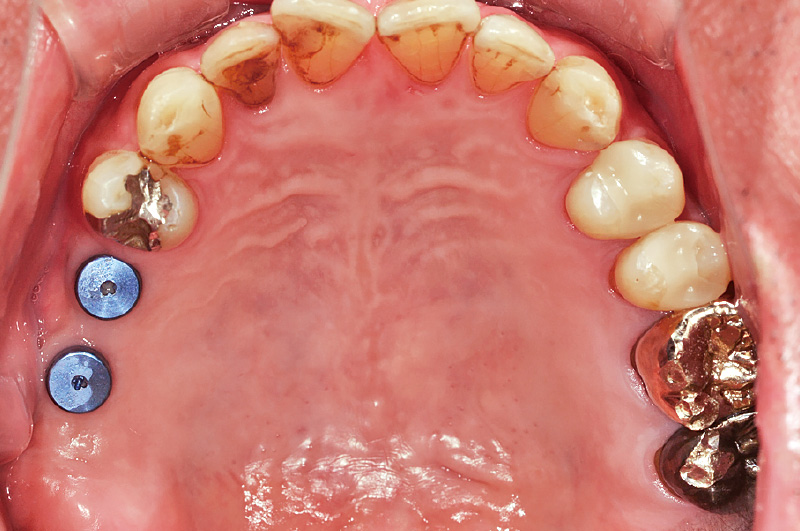

![[写真] 症例② 2次手術前](/academic/dentalmagazine/wp-content/uploads/sites/2/2025/11/195-10_photo10.jpg)

図10 症例② 2次手術前

当院にて2症例目のSPIインプラントシステムを用いた症例である。症例①と同様にインプラント埋入後、待機期間を経て2次手術前の状態を示す。 -